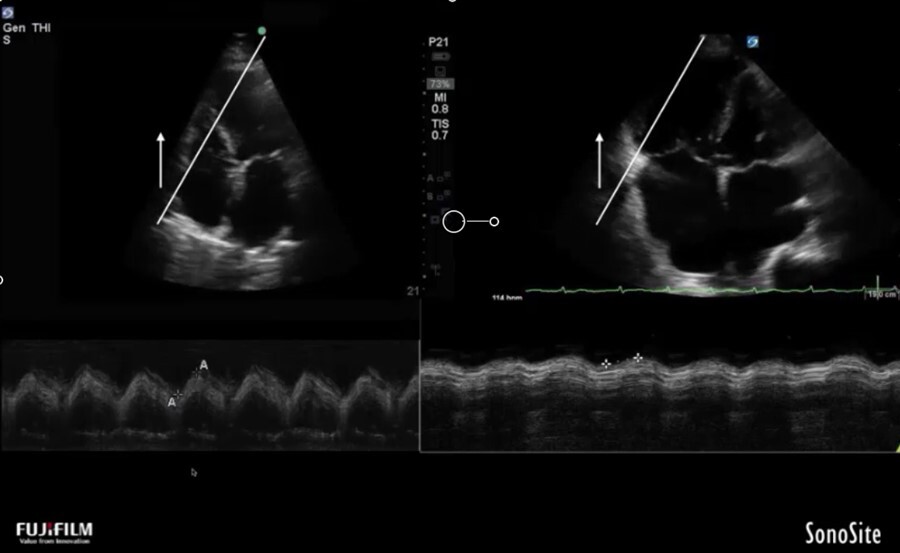

Cardiac 2 TAPSE Image